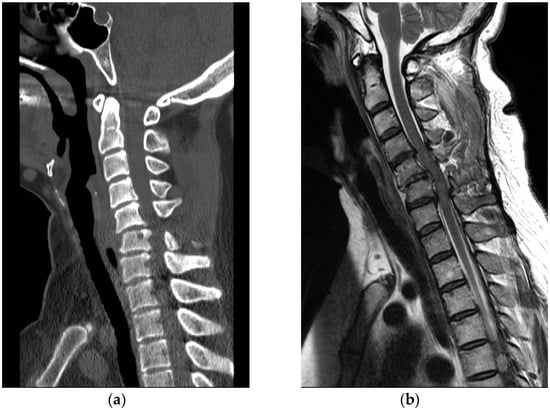

A 58-year-old healthy woman without any other medical history was doing at-home workout in her own house on 31 January 2015. The patient had been previously active and well before the accident. After training, she was hanging upside down on her inversion table. While hanging on the inversion table, she slipped and fell, hitting her head on the ground. She collapsed and immediately experienced a complete loss of body motor function. She visited the emergency room of a local medical center. Cervical spine CT revealed a bursting fracture on C6 (Figure 6a). For further evaluation, she was transferred to our hospital. Cervical spine MRI revealed heterogeneous signal change and intramedullary hemorrhage introducing compressive cervical myelopathy. (Figure 6b).

Figure 6. (a) Cervical spine CT showed C6, C7 vertebral body bursting fracture; (b) Cervical spine MRI revealed cord compression and heterogeneous signal change with hemorrhagic infiltration.